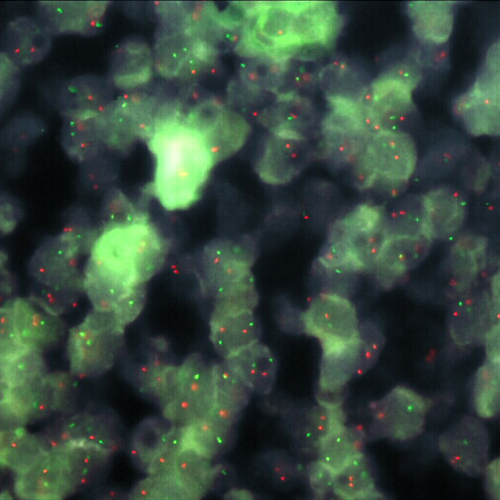

Synovial Sarcoma stained using SS18 (18q11) Break – XL for BOND (KBI-XL018).

The SS18 (18q11) Break - XL for BOND FISH probe detects genomic translocations involving the SS18 gene. SS18 (18q11) Proximal - XL and SS18 (18q11) Distal - XL are optimized to detect genomic regions proximal and distal to break points in the SS18 gene region.

When combined, both probes are used to detect translocations involving the SS18 gene at 18q11.